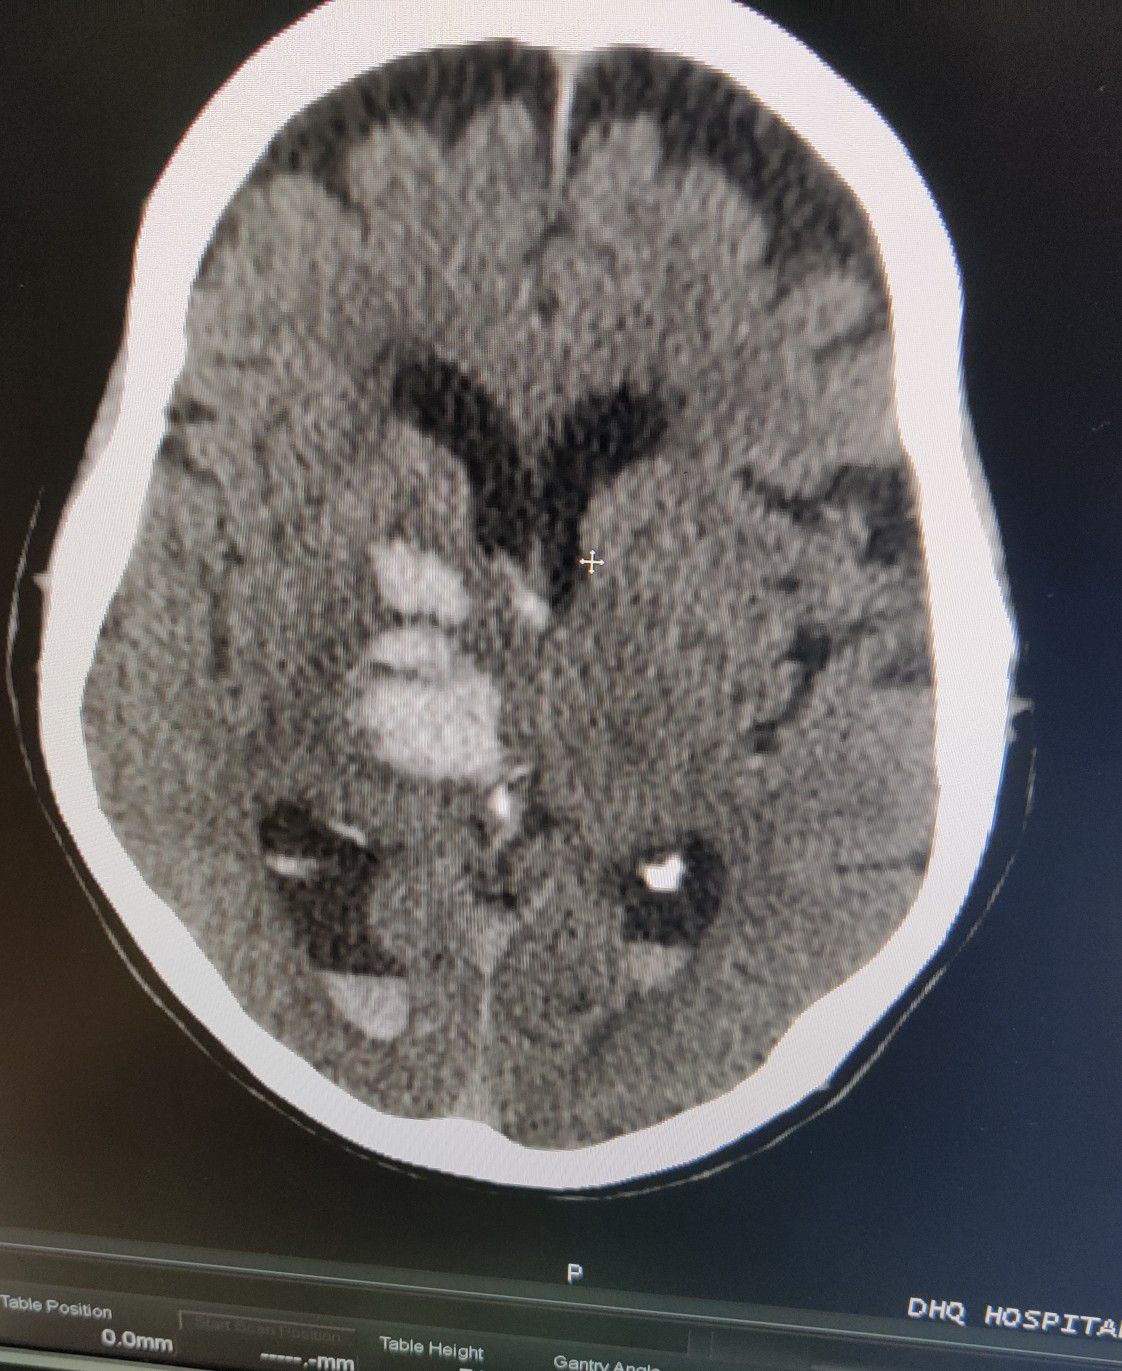

Hemorrhagic CVA

Stroke

Cva

Hemorrhagic